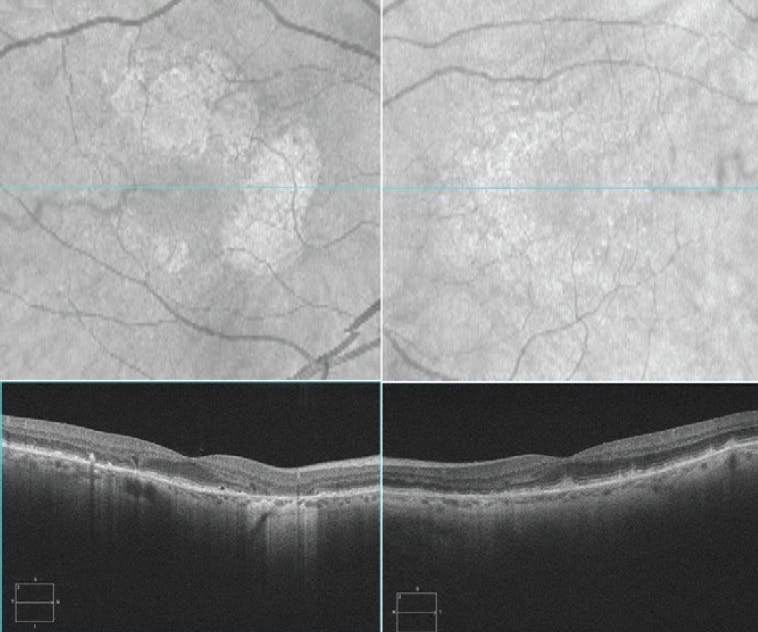

Approximately 7 years after her initial presentation, BCVA OD had reduced to CF at 3 ft and BCVA OS was 20/50 (Figure 4). Using the ZEISS Retina Workplace, I compared differences in lesion area within 5 mm of the foveal center in both eyes from two timepoints: an appointment in 2012 and an appointment in 2017. A 166% increase in lesion area within 5 mm of the foveal center OD was calculated, and full foveal involvement was observed (Figure 5). A 252% increase in lesion area within 5 mm of the foveal center OS was observed, and the foveal center was spared (Figure 6).

<p>Figure 4. Approximately 7 years after the patient’s initial presentation, BCVA was CF at 3 ft OD and 20/50 OS. A large contiguous lesion has encroached the fovea OD, and lesion area OS has advanced significantly.</p>

Figure 4. Approximately 7 years after the patient’s initial presentation, BCVA was CF at 3 ft OD and 20/50 OS. A large contiguous lesion has encroached the fovea OD, and lesion area OS has advanced significantly.